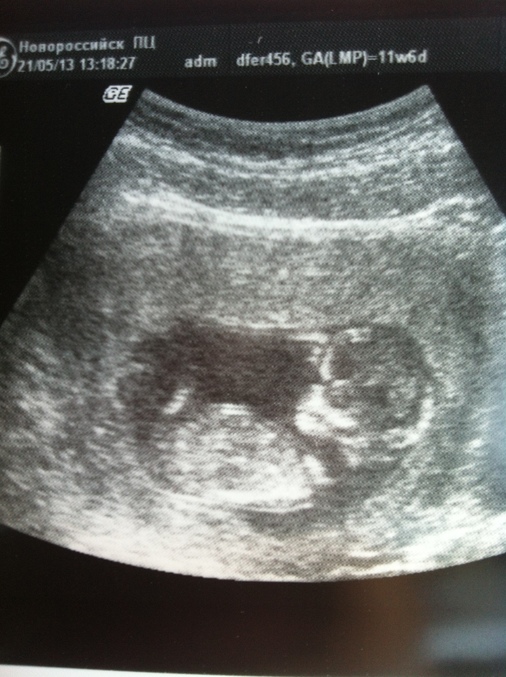

21 мая была на первом скрининге)) Сказали, что у нас все хорошо) Показали ручки, ножки и на фотке уже человечик)

Нам поставили 12 нед и з дня)